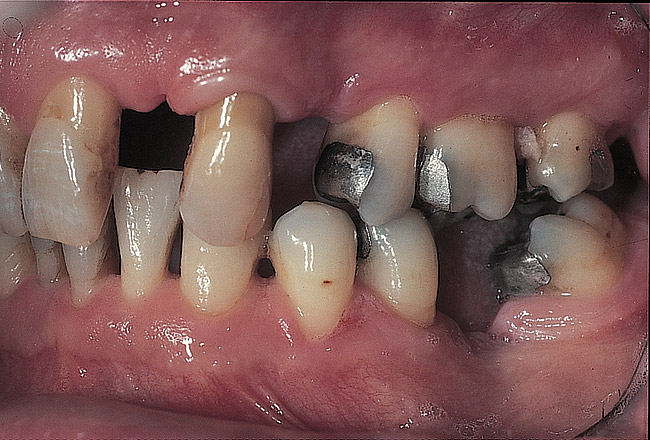

Figure 4  Facial view showing the establishment of a composite deprogrammer.

Figure 4